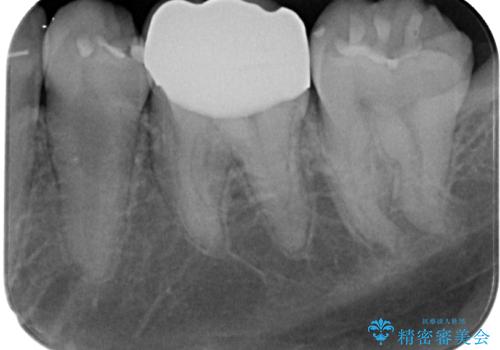

拡大鏡視野下でコンポジットレジン、虫歯の除去を行い、オールセラミッククラウンに適した形に整えました。

歯と歯茎の間に圧排糸と言われる糸を入れてシリコーン印象材にて精密な型どりをしました。

虫歯による不快な症状がなくなり喜んでいただきました。セラミックの被せものが入った後の違和感なく過ごせているそうです。矯正治療終了直後の被せもの治療なのでリテーナーの作成回数をできるだけ少なく迅速に行うことを考慮して治療を行いました。

今後、ホワイトニングを行う予定なので、患者様のご希望により、周りの歯に比べてあえて白い被せものを作成しました。